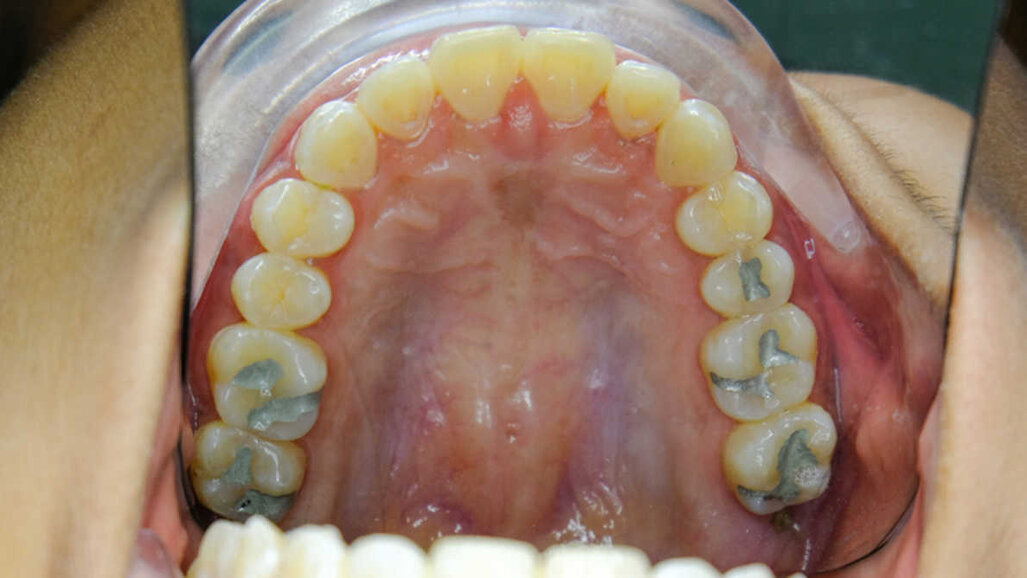

SAN JUAN, Puerto Rico/SPRING, Texas, U.S.: Mercury in dental amalgam contributes to global mercury pollution in multiple ways, such as the illegal diversion of dental mercury into the artisanal and small-scale gold mining industry, crematoria emissions from the deceased and sewage sludge sold to the farmers. This mercury pollution leads to air, water and food contamination that can impact human health negatively. A recent study investigated the different pathways that release mercury from dental amalgam into the environment.

The treaty discusses the various ways - sewage sludge, cremation, burial, human waste, and artisanal and small-scale mining etc- by which dental amalgam releases mercury and impacts the environment adversely. However, according to the authors of the study, there has been very little research done on this topic, and this is the first paper to address all of the pathways through which mercury enters the environment from dental amalgam and acts as a cradle-to-grave deadly pollutant.